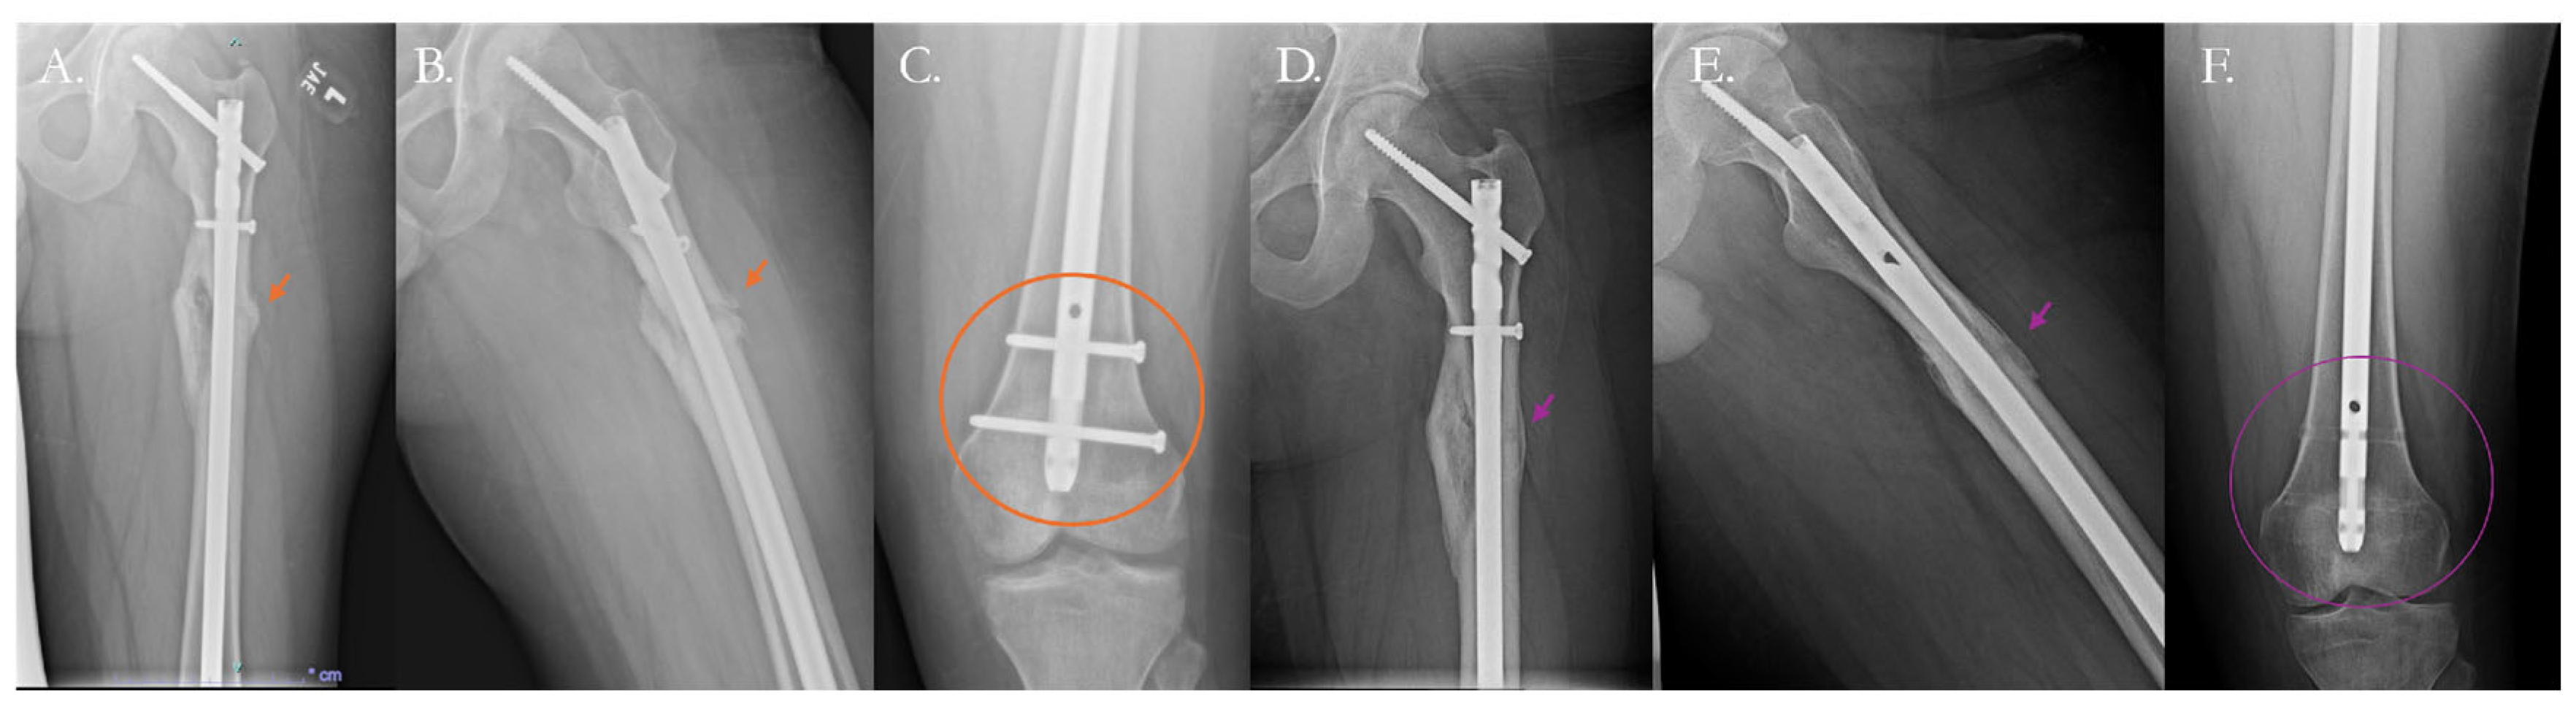

4.2.1. Traditional Surgical Approaches

- Mittal, K.K.; Gupta, H.; Kaushik, N. Reunion of Post Nail Aseptic Non-Union of Diaphyseal Femoral Fractures by Augmentation Plating, Decortication and Bone Grafting–Replacement for Exchange Nailing. Injury 2021, 52, 1529–1533. [Google Scholar] [CrossRef]

- Fragomen, A.T.; Wellman, D.; Rozbruch, S.R. The PRECICE Magnetic IM Compression Nail for Long Bone Nonunions: A Preliminary Report. Arch. Orthop. Trauma. Surg. 2019, 139, 1551–1560. [Google Scholar] [CrossRef] [PubMed]